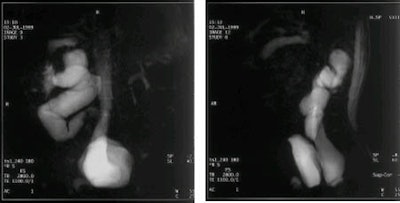

Determinaron que una hora antes del examen, un paciente en ayunas debe ingerir una mezcla de contraste de tres partes de leche con una parte de zumo de arándanos puro. Para los lactantes, el agente de contraste se administra por medio de una biberón.

Rivoal comprobó que el procedimiento tenía un efecto sedante en el niño, inducía un buen estado de hidratación y aumentaba la diuresis para el estudio de imagen. Para los estudios de imagen de los niños que todavía se alimentan al pecho, recomendaba que el niño tomara zumo de arándanos edulcorado diluido antes de la lactación.